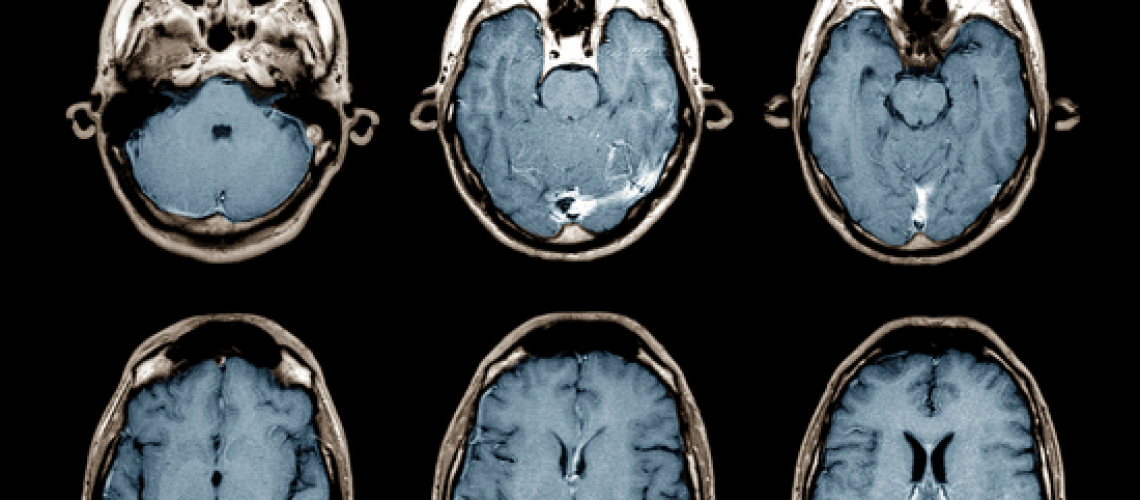

בדיקות MRI הן אחד הכלים האבחוניים המדויקים ביותר ברפואה המודרנית. הן מאפשרות לקבל תמונות מפורטות של רקמות רכות כמו המוח, עמוד השדרה, המפרקים וכלי הדם, ללא חשיפה לקרינה מייננת. במקרים מסוימים נעזרים בחומר ניגוד בשם גדוליניום כדי לשפר את יכולת ההדמיה ולזהות ממצאים עדינים במיוחד.

גדוליניום הוא יסוד מתכתי ממשפחת המתכות הנדירות. בצורתו הטהורה הוא עלול להיות רעיל, אך לשימוש רפואי הוא נקשר למולקולות אחרות ויוצר תרכובות יציבות שנקראות "חומרי ניגוד על בסיס גדוליניום". לאחר ההזרקה לוריד, החומר נע במחזור הדם ומדגיש אזורים שבהם קיימת זרימת דם מוגברת או חדירות חריגה של כלי דם, כמו בגידולים, דלקות או מוקדי דימום ישנים.

• הדמיית מוח – להבדיל בין גידול, דלקת או שאריות של אירוע מוחי.